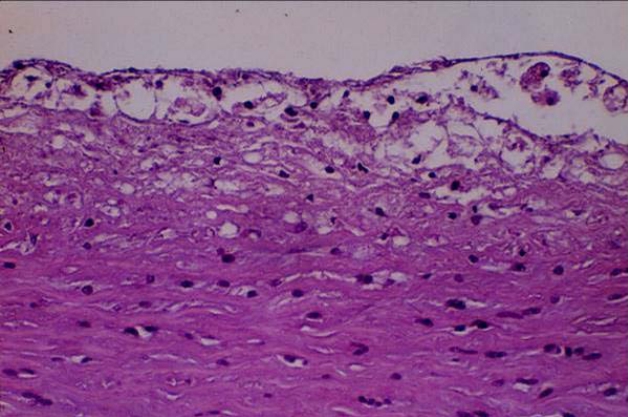

动脉粥样硬化性血栓形成过程

动脉粥样硬化脂纹脂斑

其中Ⅱ型及Ⅲ型与冠状动脉粥样硬化性心脏病关系最密切。高脂蛋白血症Ⅱ型患者的生化特点是血浆中β脂蛋白大量增加,胆固醇和磷脂也增加,甘油三脂正常或微增。这些胆固醇和脂质在动脉管内沉着,内膜呈现局限性增厚,形成斑块,然后发生崩溃,形成溃疡和软化,分解出一种黄色粥样物质,故称“粥样硬化”。此后有纤维组织增生,并可有钙质沉着,或发生局部血栓形成,内膜凹凸不平,管腔狭窄,使管壁硬化。若硬化发生于大动脉,对血液供应不会产生影响;若发生于中型动脉(如冠状动脉、脑动脉、肾动脉等),则引起相应脏器供血不足,甚至发生梗阻。所以高脂蛋白血症Ⅱ型的最危险并发症是早发的冠状动脉粥样硬化,常并发心绞痛与心肌梗死。